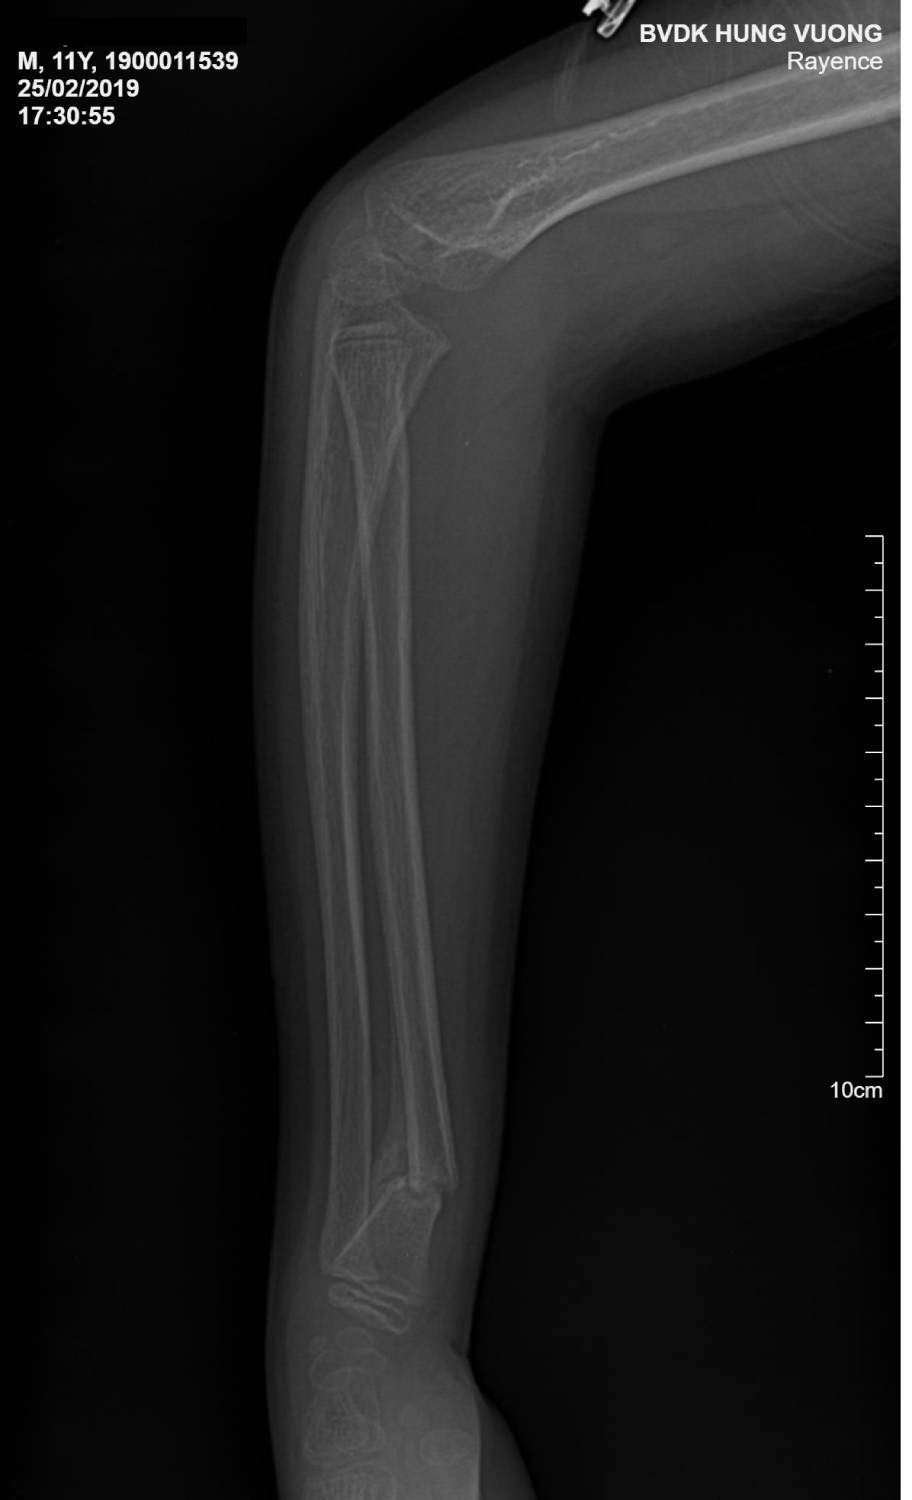

Hình ảnh cho thấy tay cháu bé biến dạng. (Ảnh bệnh viện cung cấp)

Kết quả chụp x-quang cẳng tay phải của bệnh nhi cho thấy hình ảnh gãy kín đầu dưới xương quay, cần được phẫu thuật cố định lại.

Hình ảnh chụp x-quang cho thấy tay cháu bé gãy kín đầu dưới xương quay, cần được phẫu thuật cố định lại xương quay. (Ảnh bệnh viện cung cấp)